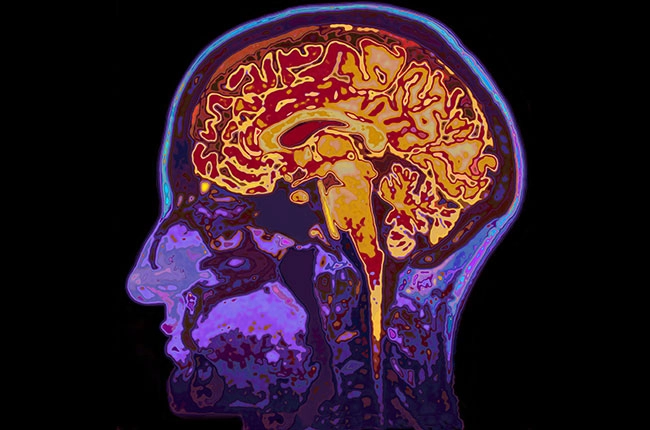

‘Brain imaging studies, however, have thus far failed to provide a convincing neural correlate that could underpin any protective effect.’